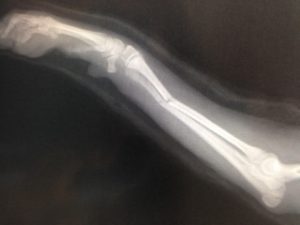

事故が起こったのは今年のゴールデンウィーク。

トイプードルの生後4か月の女の子が、家族旅行で訪れた蓼科高原のドッグカフェで、

飼い主さまの手から落ちてしまい、左前脚を骨折してしまいました。

近くの動物病院で応急処置を施してもらった上で、帰京後、当院に来院されました。

すぐに骨折部にプレート装着手術を行ない、なんとか歩行が可能に(写真上右)。

数か月が経過し、骨折部がしっかりと接合したのを確認し、

先日、プレートの除去手術を行ないました(写真下)。